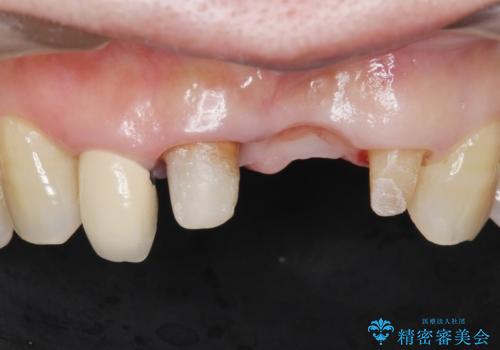

- 上下の前歯が抜けそうだとのことで来院されました。

精査したところ、動揺の著しい上下の前歯は重度の歯周病により保存不可能と判断しました。

ブリッジ、インプラント、義歯の選択肢の中で上下前歯ともにブリッジをご希望されました。

抜歯後歯肉の治癒を十分に待ったのち、ブリッジによる補綴治療を行いました。